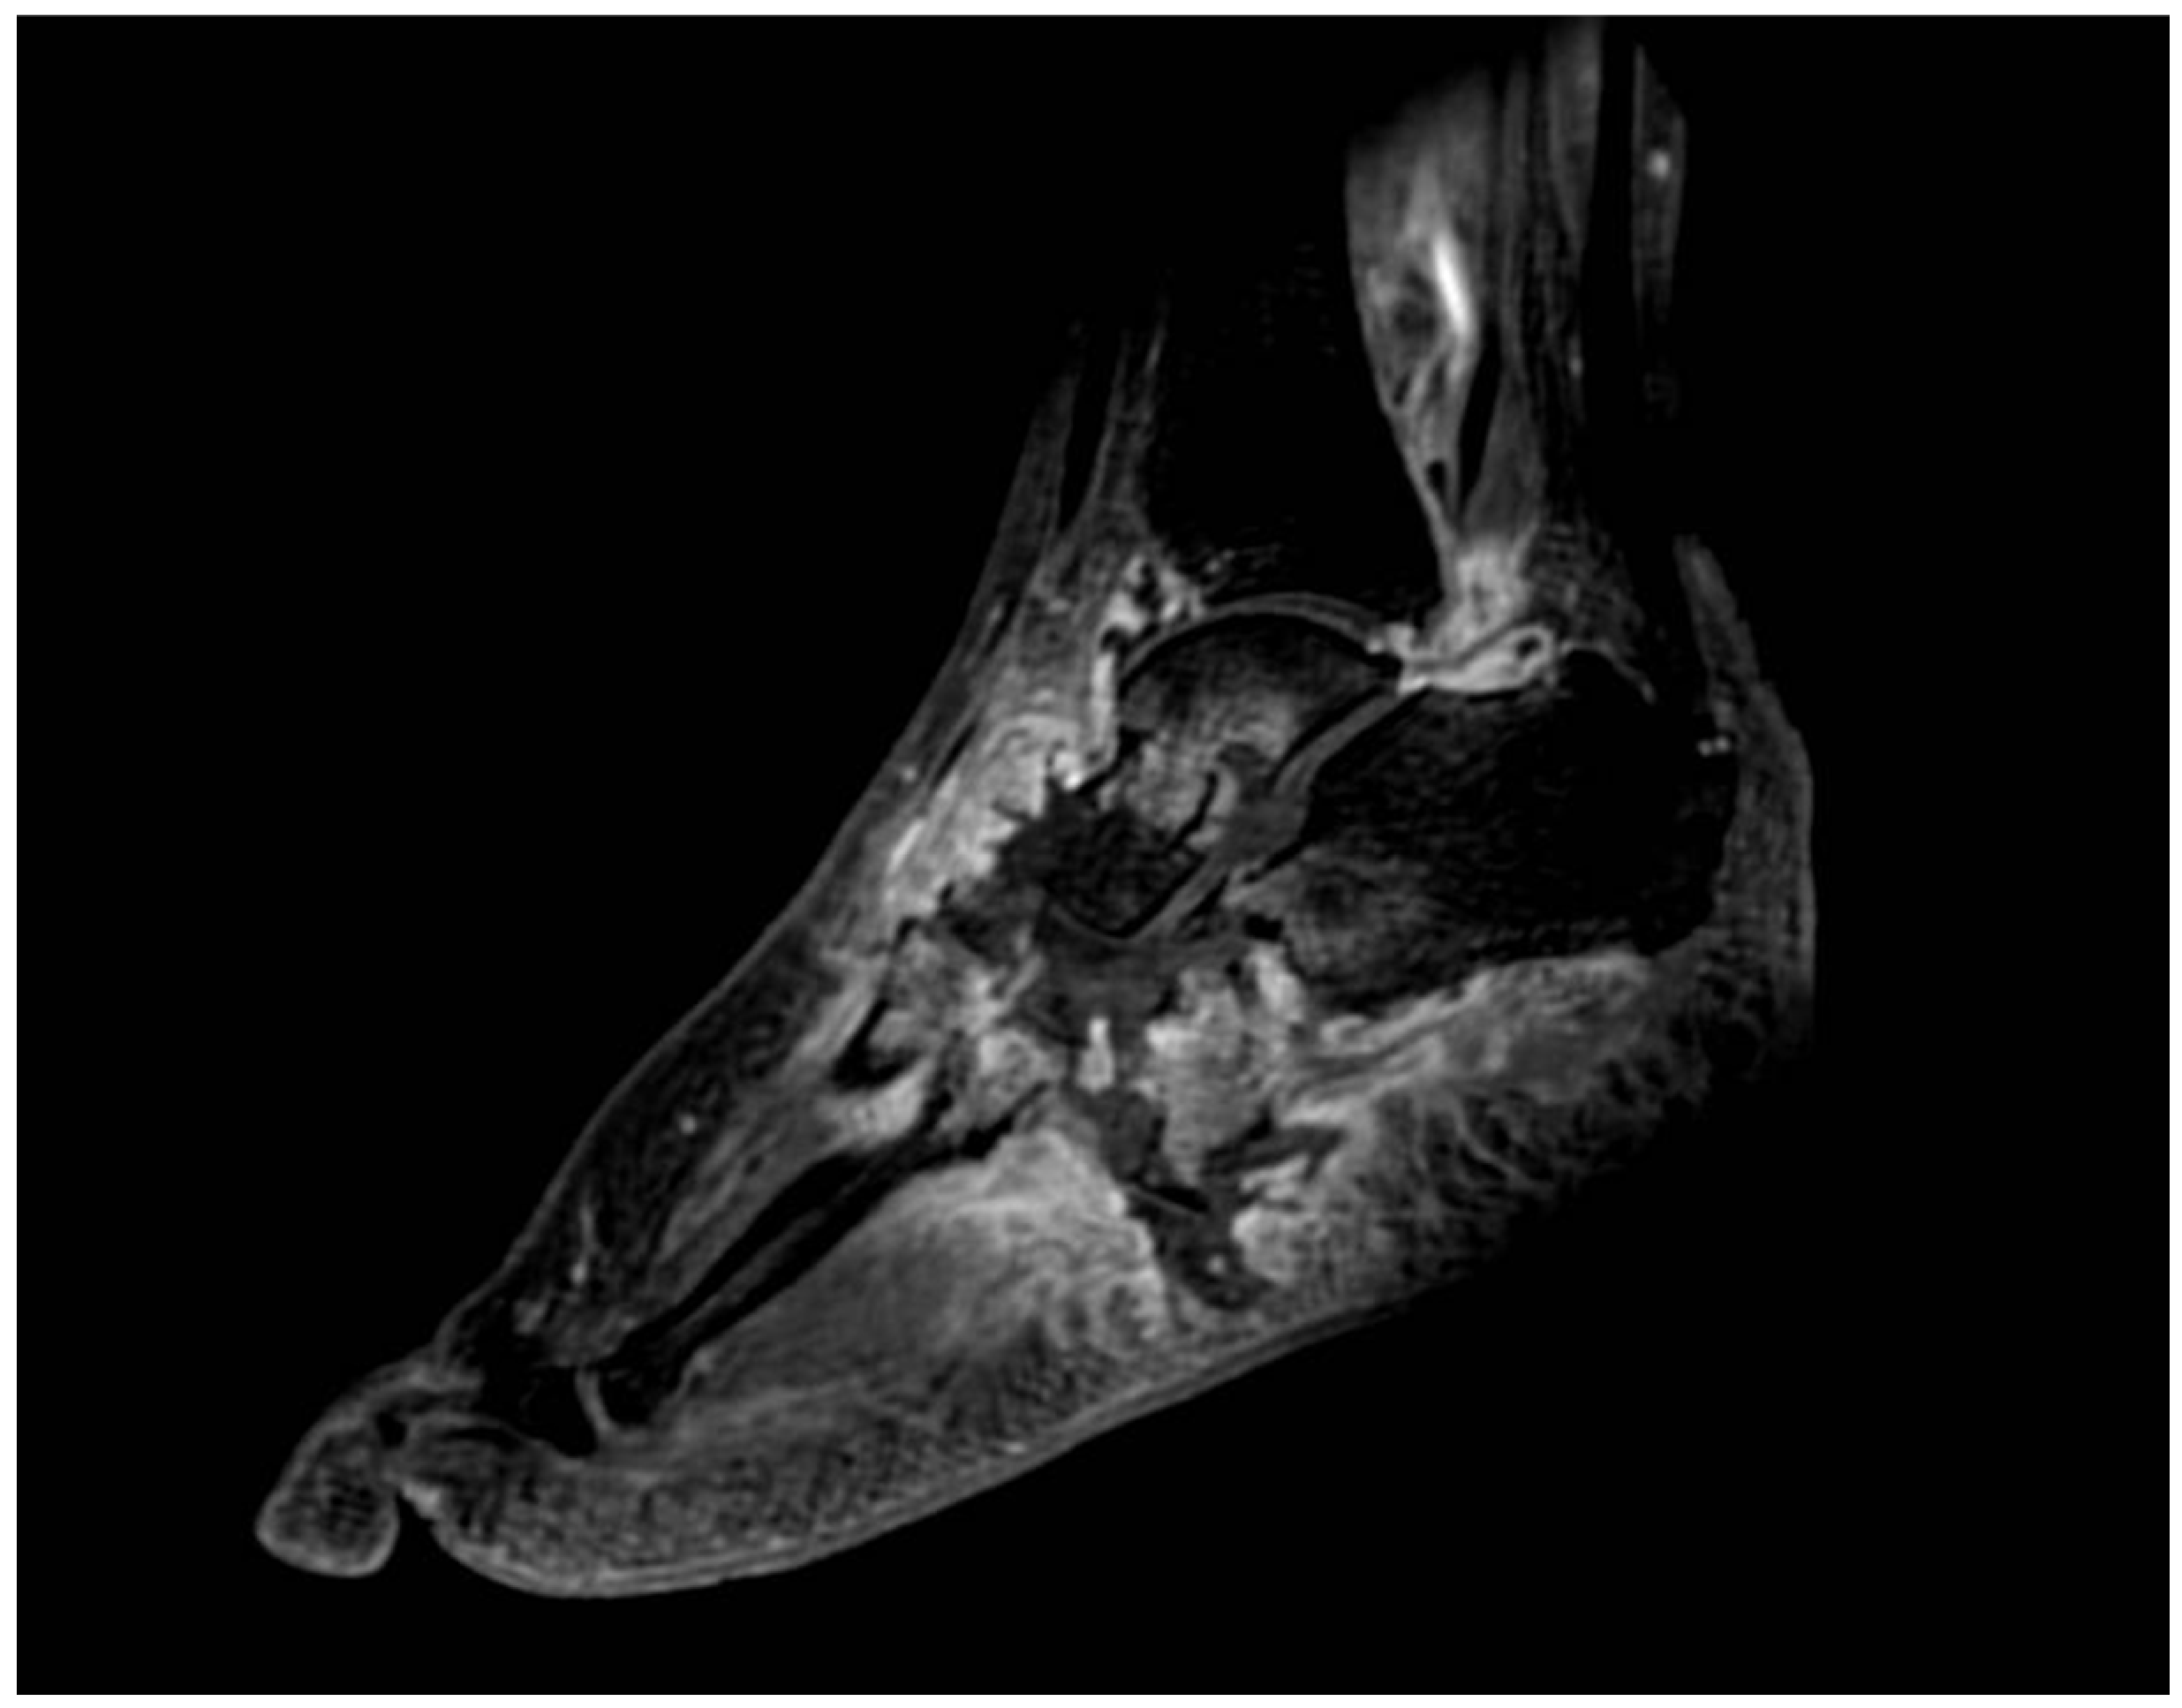

4. Magnetic Resonance Imaging